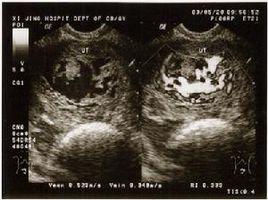

小婷腹部日渐隆起,7月底,小婷怀孕六个多月,突然出血了,量还很大。丈夫吓坏了,赶紧把她送到了东阳市人民医院。检查结果却让人大跌眼镜,B超检查显示,子宫内充满了水泡状的东西,就跟葡萄一样,根本没有胎儿,这就是常说的葡萄胎。

医生解释说,小婷这种情况属于妊娠后胎盘绒毛滋养细胞增生,间质高度水肿,形成大小不一的水泡,水泡间相连成串,形状就像葡萄一样。发病率大约为1/1000。换句话说,就是胎儿没正常发育。

6、目前B超检查能够帮助医生更早地诊断出葡萄胎。在闭经8周前后,B超监测,未发现有胎囊、胎心及胎儿。孕周、甚至18周仍不感有胎动,听不到胎心。B超扫描显示雪片样影像而无胎儿影像。